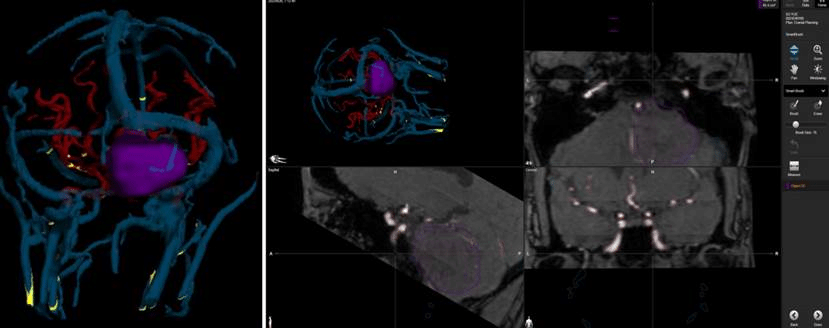

高成教授与患者充分沟通和心理疏导,减少患者焦虑的同时,与电生理监测团队一起制定了周密和详细的手术预案。术中高成教授听神经瘤MDT团队凭借精湛的手术技巧,通过仔细分离覆盖在听神经瘤表面的“膜性结构”和肿瘤粘连紧密的面神经和听神经,在电生理监测的辅助下全切肿瘤的同时,顺利保住了患者的面神经和听神经。术后王女士无任何面瘫,听力较术前明显好转,并顺利出院。

目前,ac米兰官网中文网站一院神经外科高成教听神经瘤MDT团队每年完成50余例听神经瘤手术。经过多年的实践总结,结合目前国内外最新的进展,已经摸索出了一套仔细分离覆盖在听神经瘤表面的“膜性结构”,保留面神经、听神经的解剖和功能的完整经验,面神经的解剖保留率在95%以上,达到了国内领先水平。